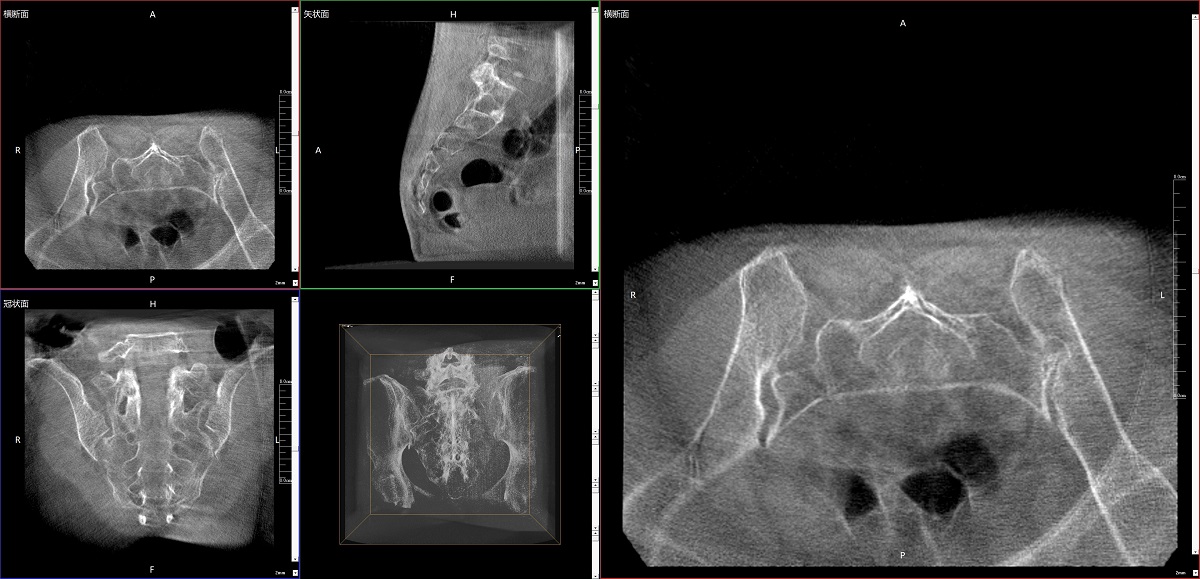

在骨科手術中,影像相當于醫生的“眼睛”,要先“看得清",才能“算得準” “打得穩”。普愛醫療第三代平板三維C形臂協同醫院創傷導航機器人已開展多例“骨盆骨折微創手術”,成為上海市第七人民醫院手術技術創新的一大亮點。

普愛醫療第三代平板三維C形臂出色的二維透視和術中三維成像效果,為機器人提供了精確的術中影像依據,協同提升手術整體的精準度和效率,為患者帶來了更安全、更高效的醫療服務體驗。